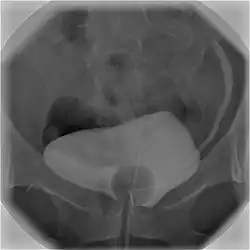

Cystography image showing contrast in the urinary bladder and left ureter (right side of image).

Cystourethrography is a radiographic, fluoroscopic medical procedure that is used to visualize and evaluate the bladder and the urethra.[1] Voiding and positive pressure cystourethrograms help to assess lower urinary tract trauma, reflux, suspected fistulas, and to diagnose urinary retention. Magnetic imaging (MRI) has been replacing this diagnostic tool due to its increased sensitivity.[2] This imaging technique is used to diagnose hydronephrosis, voiding anomalies, and urinary tract infections in children. abnormalities.[3]